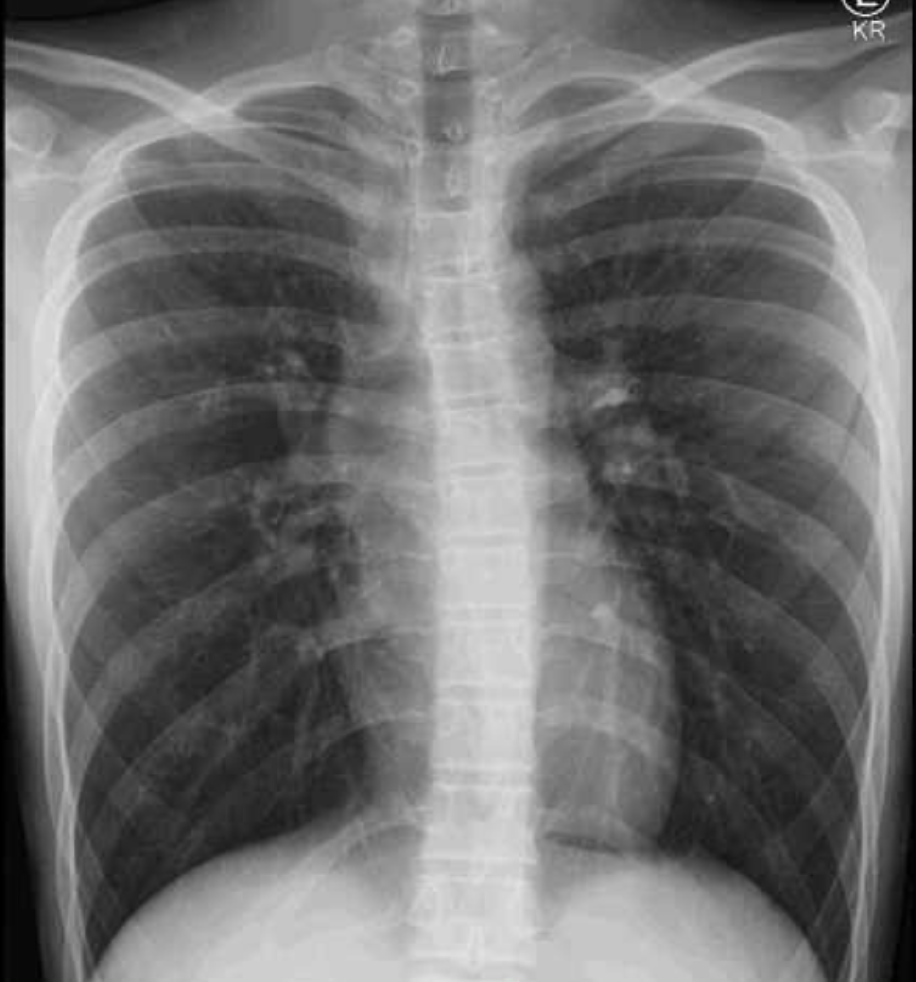

Prioritize Images |

Image interpretation is a top failure point |

Weekly ECG/X-ray/ultrasound practice sets |

Master Image-Based Questions

ABEM exams are pictorial-heavy: ECGs, X-rays, CTs, ultrasounds. Weak image interpretation is a top cause of failure.